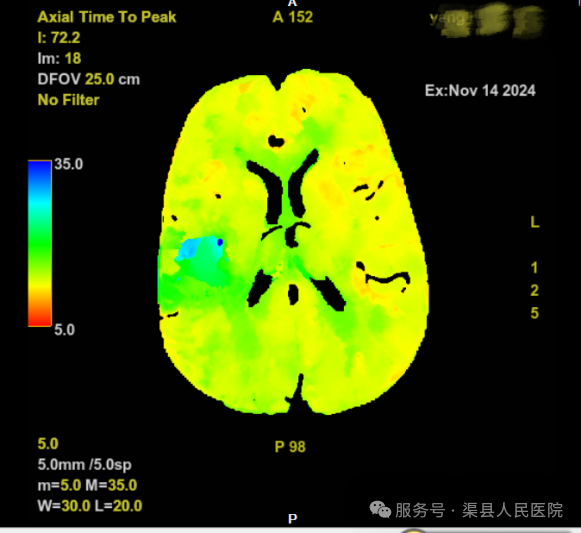

在影像联合科的全力配合下,即刻得到结果:核心梗死区:0ml,缺血半暗带:23.7ml,Mismatch比值:无穷大。结合患者的抽血结果和《中国急性缺血性卒中诊治指南》(2023版),患者具有静脉溶栓指征,立即于CT室进行溶栓治疗。

CT灌注成像(CT Perfusion,CTP)是评估脑梗死组织窗的检查,提供延长静脉溶栓、动脉取栓时间必不可少的指导证据。CTP是指在静脉注射对比剂的同时对选定层面通过连续多次同层扫描,以获得该层面每一像素的时间-密度曲线,其曲线反映的是对比剂在该器官中组织浓度的变化,间接反映组织器官灌注量的变化。

1、脑缺血性病变:灌注成像分析脑血液动力学改变,通过评价脑血流(CBF)、脑血容量(CBV)及平均通过时间(MTT)来描述早期缺血性脑卒中患者脑血流低灌注区、梗死区及缺血半暗带区,由此获得较完整的早期卒中的诊断信息。